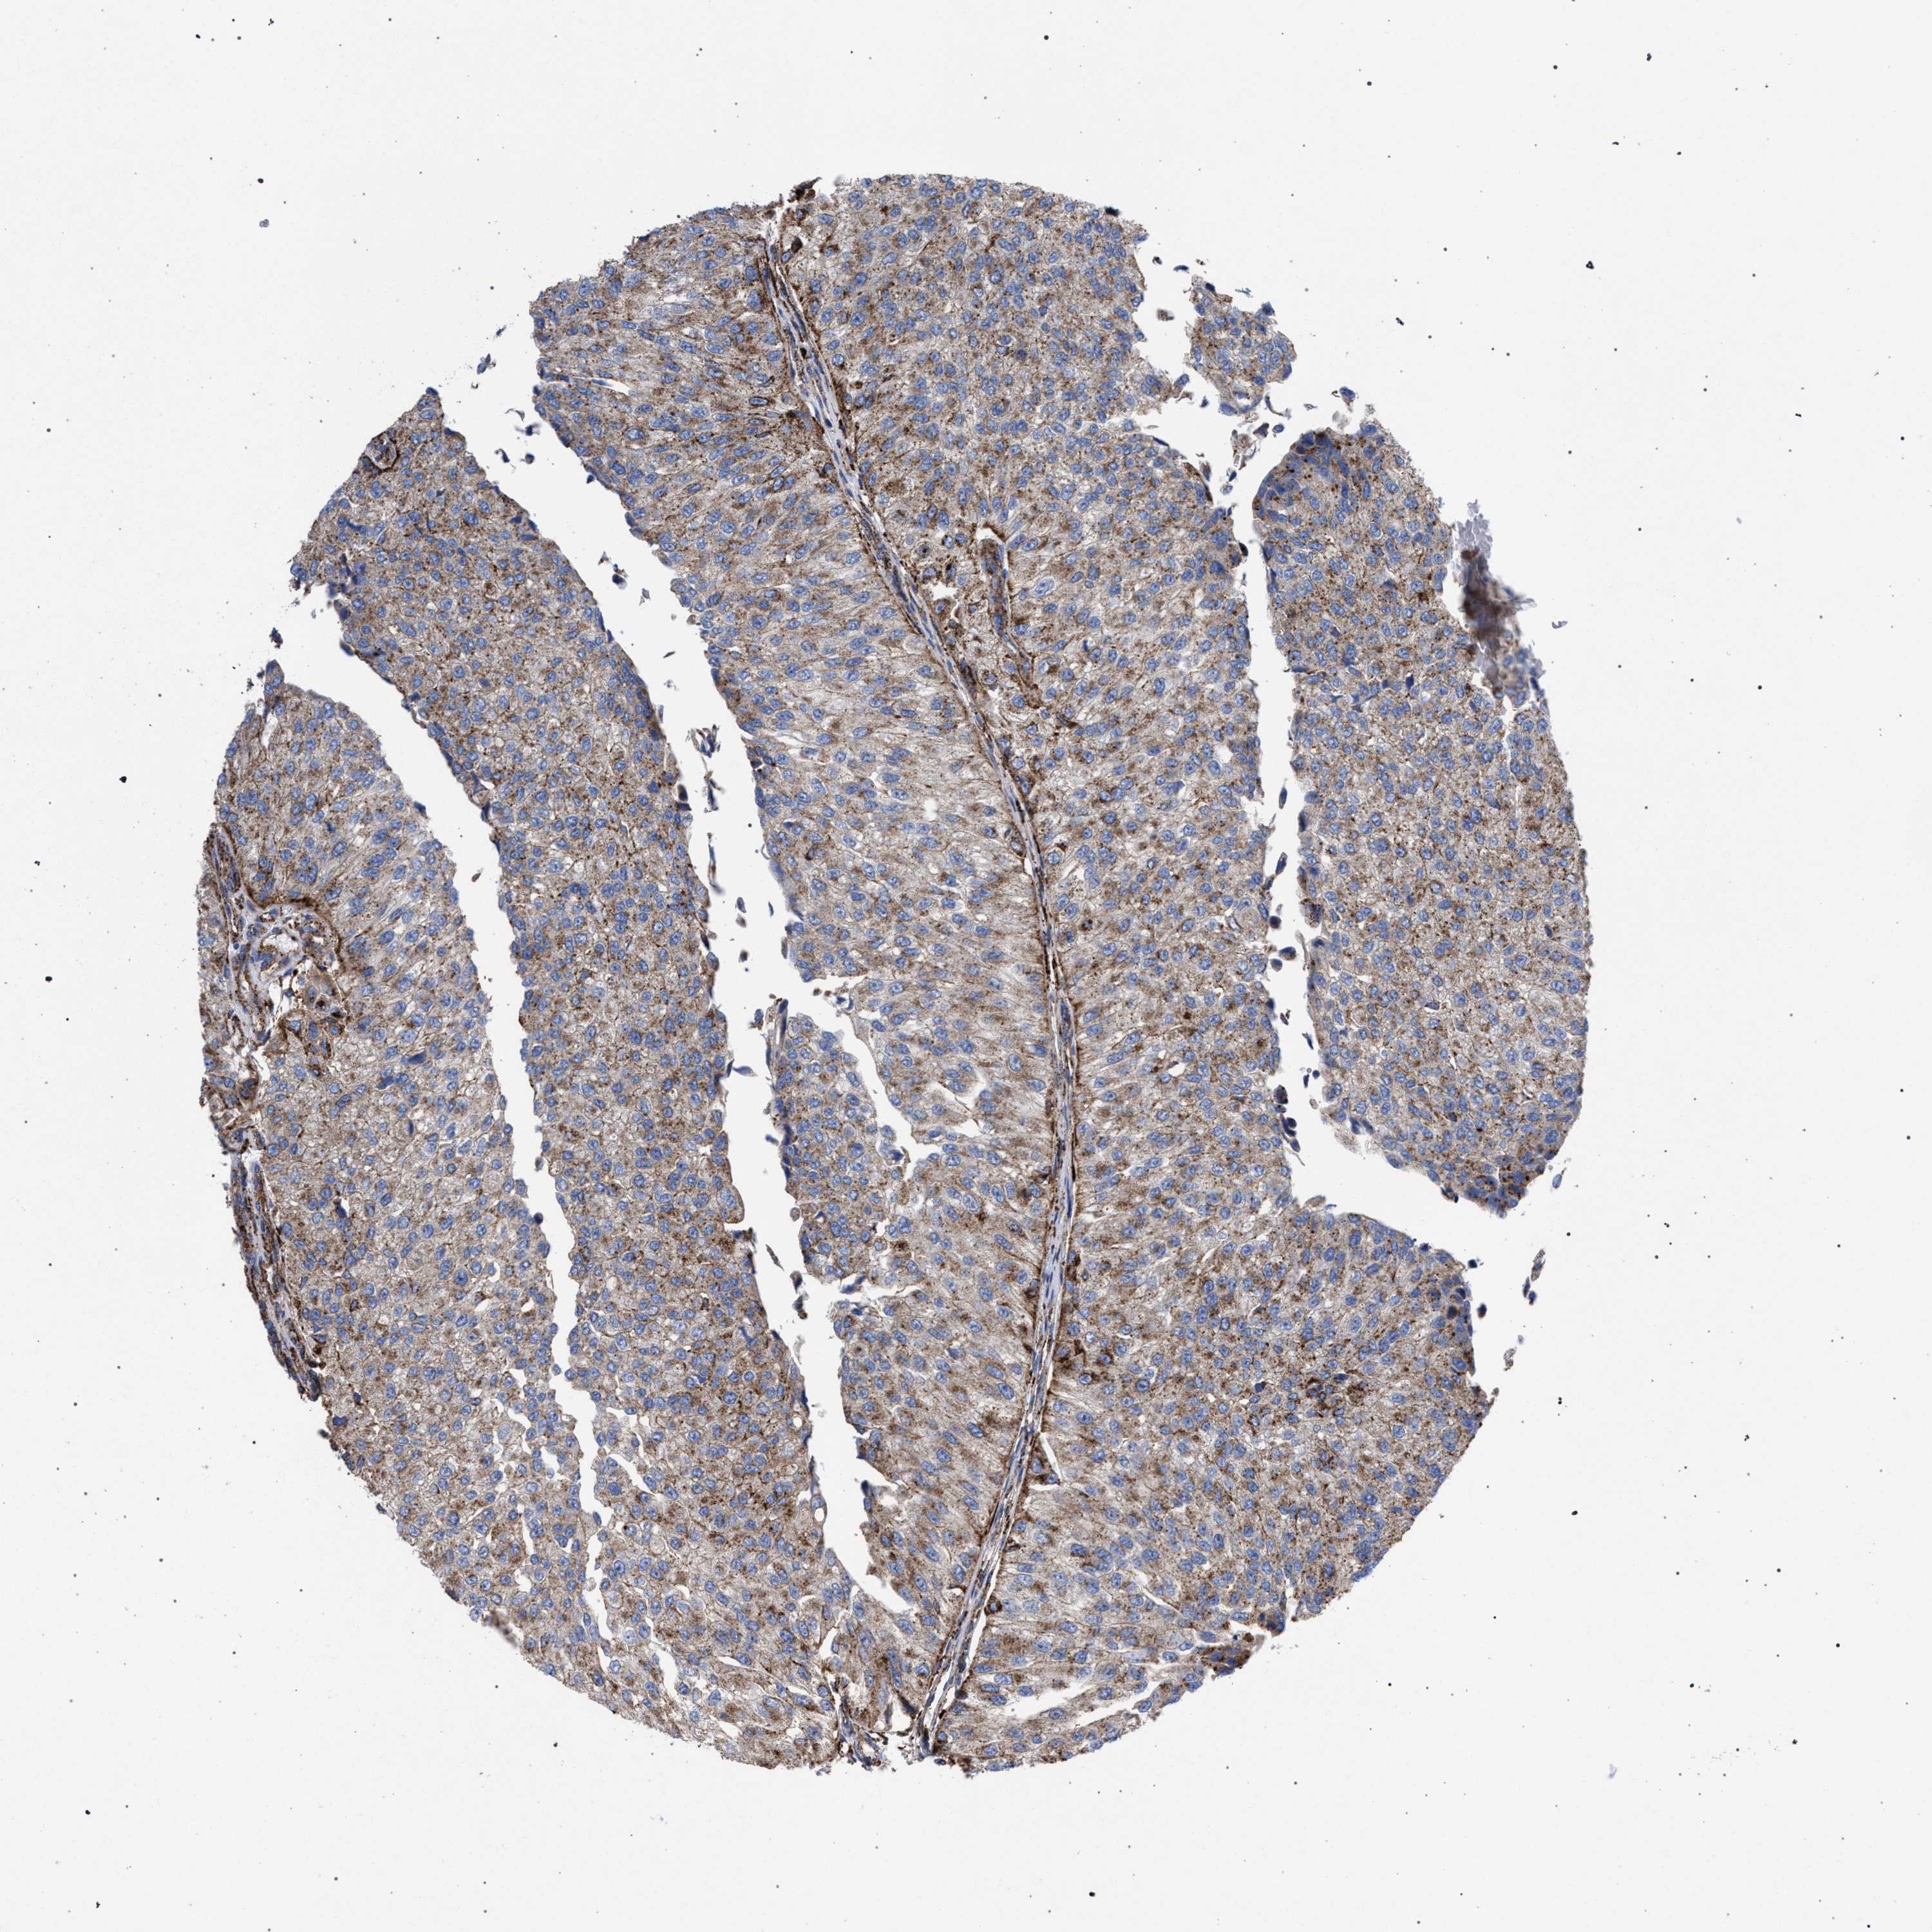

UROTHELIAL CANCER - Protein expressioni

A mouse-over function shows sample information and annotation data. Click on an image to view it in a full screen mode. Samples can be filtered based on level of antibody staining by selecting one or several of the following categories: high, medium, low and not detected. The assay and annotation is described here.

Antibody stainingi

Antibody staining in the annotated cell types in the current human tissue is reported as not detected, low, medium, or high, based on conventional immunohistochemistry profiling in selected tissues. This score is based on the combination of the staining intensity and fraction of stained cells.

Each image is clickable and will lead to virtual microscopy that enables deeper exploration of all samples and also displays staining intensity scores, fraction scores and subcellular localization as well as patient and tissue information for each sample.

Antibody HPA021546

Staining

High

Medium

Low

Not detected

Intensity

Strong

Moderate

Weak

Negative

Quantity

>75%

75%-25%

<25%

None

Location

Nuclear

Cytoplasmic/membranous

Cytoplasmic/membranous,nuclear

Urothelial carcinoma, Low grade